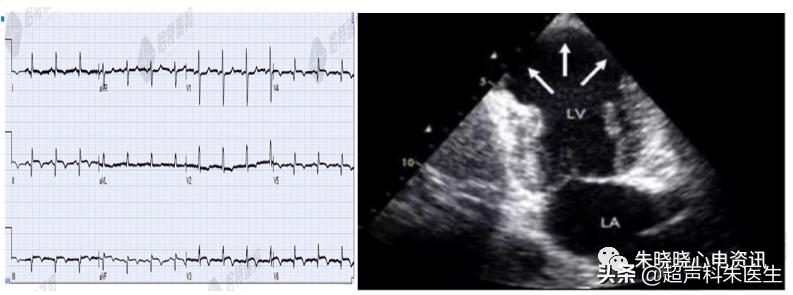

如图9:76岁老年女性,两个月前爬山时感胸闷、憋气,无放射性疼痛,休息几分钟后缓解。1周前因搬家劳累再发胸骨后闷痛,憋气 。既往高血压、高脂血症10余年,心房颤动2年。入院后行常规心电图示广泛导联T波倒置。

图9:广泛导联T波倒置

图10:患者的心脏彩超

患者的心脏彩超见:左房增大,室间隔及左室壁厚度呈渐进性增厚,心尖为著 (中间段厚 18 mm,心尖部厚24.5 mm) ,室间隔运动幅度轻度减低,LVEF正常

冠脉造影示:右冠状动脉中段 (RCAm) 管腔不规则,狭窄50%,并取左室室壁处行心肌组织活检。

心肌活检示:组织学染色下可见排列紊乱、肥大的心肌细胞。

心尖肥厚型心肌病心电图可见:左胸导联高大R波伴巨大倒置T波;

可能的机制:心尖部心肌局部肥厚导致QSR波向量向左前增大,造成左胸导联R波增高,同时伴有复极异常,呈明显的心前区 (V3~V4导联) T波倒置。

而心肌缺血时,无明显R波增高,T波倒置常位于广泛胸前导联,无特异性。